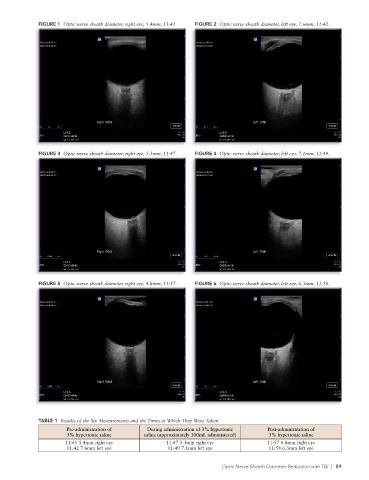

can detect elevated ICP at its inception, before papilledema Because of the ongoing critical resuscitation, only one mea-

develops; it can be completed rapidly, at the point of care and surement was taken per eye at each time period; a total of six

can be repeated to trend values; other modalities requiring measurements were taken (Figures 1–6). In two of the images,

equipment (like CT or MRI scanners) or expertise (e.g., neu- slight variances appear secondary to the time pressure under

rosurgery) are often not available to combat casualties; and which the measurements were made—in Figure 3, the depth

measuring ONSD is a skill that can be acquired relatively was measured at 3mm, but the caliper at the globe was inad-

quickly. 4,7,9,19 vertently moved after the measurement was completed, mak-

ing the measurement appear to have been taken at 3.8mm; in

Against this backdrop, we report the case of a patient present- Figure 5, the caliper measurement of 3mm was not perpen-

ing as a level 1 trauma patient with a penetrating traumatic dicular to the optic nerve, thereby minimally shortening the

head injury who received a bolus of 250mL 3% hypertonic retrobulbar distance. The results of the six measurements and

saline to treat presumed elevated ICP. ONSD measurements the times at which they were taken are presented in Table 1.

taken before, during, and after administration of this hyper-

tonic saline bolus showed a reduction in the ONSD of 0.6mm Following transfer, the patient was treated nonoperatively and,

in the right eye (from 5.4 to 4.8mm) and 1.3mm in the left eye at the time of writing, remains intubated and ventilated in a

(from 7.6 to 6.3mm) within 20 minutes. To our knowledge, long-term acute care facility. Efforts were made to locate the

During the patient’s resuscitation, three ultrasound measure- in ONSD after administration of 3% hypertonic saline. In a

ments of the ONSD were performed over a 17-minute period prospective, non-randomized trial in an emergency depart-

before, during, and after administration of the 3% hypertonic ment, Duyan and Vural measured ONSD in 60 patients with

saline bolus. The images were acquired by an experienced op- symptomatic hyponatremia, before and after the patients re-

erator, and the measurements were taken by a trainee under ceived either one or two boluses of 150mL 3% hypertonic sa-

the experienced operator’s supervision, using a Sonosite PX line. They found a statistically significant reduction in ONSD

cart-based ultrasound system (Fujifilm Sonosite, Bothell, WA) following treatment with hypertonic saline, although they did

with a 19-5MHz linear probe and ophthalmic settings. With not report how long after the hypertonic saline treatment the

the patient in the supine position, copious amounts of gel were second ONSD measurement was taken. 8

placed on the patient’s closed upper eyelids to facilitate imag-

ing. Care was taken not to exert pressure on the globe. The At least two studies have reported an immediate and real-time

probe was angled to bring the optic nerve into view with the reduction in ONSD with a concomitant drop in ICP. Over

lens where possible because the patient could not cooperate a period of about 6 months, Chen et al. recruited a conve-

with the examination. The ONSD was measured in the trans- nience sample of 84 patients who required outpatient lumbar

verse view at a depth of 3mm behind the globe. punctures for diagnostic purposes, and they performed ONSD